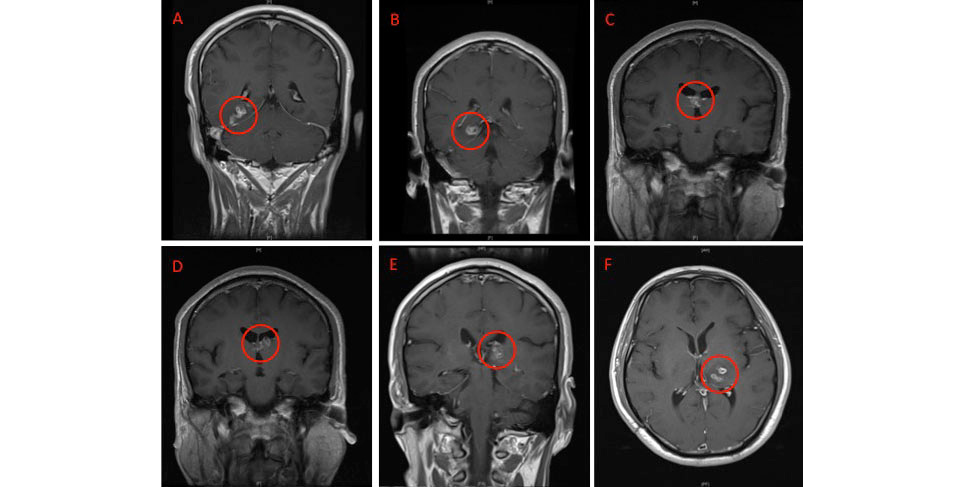

💉💉 The New York Times ran a widely reported story yesterday headlined, “Morgan Spurlock, Documentarian Known for ‘Super Size Me,’ Dies at 53.” They are trying so hard to hide jab injuries, they threw fast food under the narrative bus.

In case it wasn’t clear, the sub-headline darkly hinted at a sodium-fueled cause of death: “His 2004 film followed Mr. Spurlock as he ate nothing but McDonald’s for a month. It was nominated for an Oscar, but it later came in for criticism.”

The article’s first seven paragraphs described in glorious detail Spurlock’s infamous experiment of only eating at McDonald’s for a month, concluding, “At the end of the month, he was 25 pounds heavier, depressed, puffy-faced and experiencing liver dysfunction.”

Despite devoting dozens of column inches to his truncated life, all the Times had to say about the fast-food survivor’s death was this: Spurlock “died on Thursday in New York City. He was 53. His brother Craig Spurlock said the cause was complications of cancer.”

Aha — cancer! He survived his infamous MacDonald’s experiment, but Morgan couldn’t survive the jabs. He should’ve lived to make a film called “Superjab Me!”:

Morgan was only 53 and had two sons, Laken and Kallen, who are now fatherless. The ocean of ink eulogizing Morgan’s life supersized all the coverage he didn’t get during the last twenty years of continuous documentary filmmaking following his independent hit in 2004.

Media wanted so badly to link Morgan’s month of fast-food dining to his death from turbo cancer twenty years later, but given the intervening decades, the best they could do was hint around. But, we know. Accountability is coming. Morgan will get his revenge.